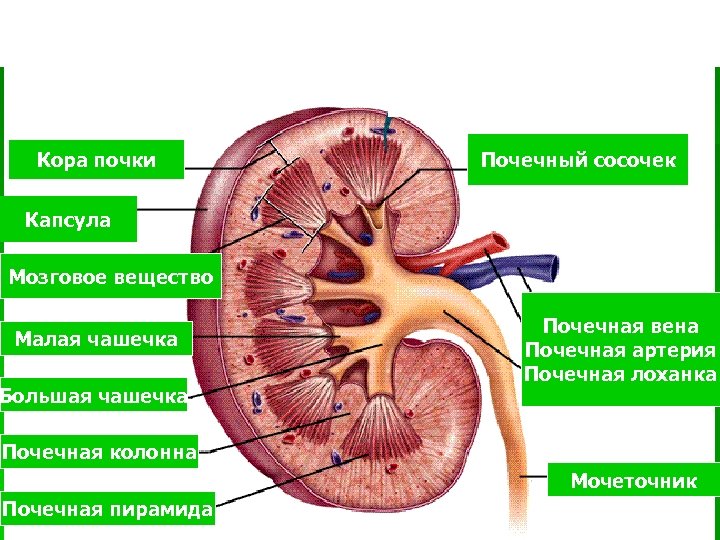

Кора почки Почечный сосочек Капсула Мозговое вещество Малая чашечка Большая чашечка Почечная вена Почечная артерия Почечная лоханка Почечная колонна Мочеточник Почечная пирамида